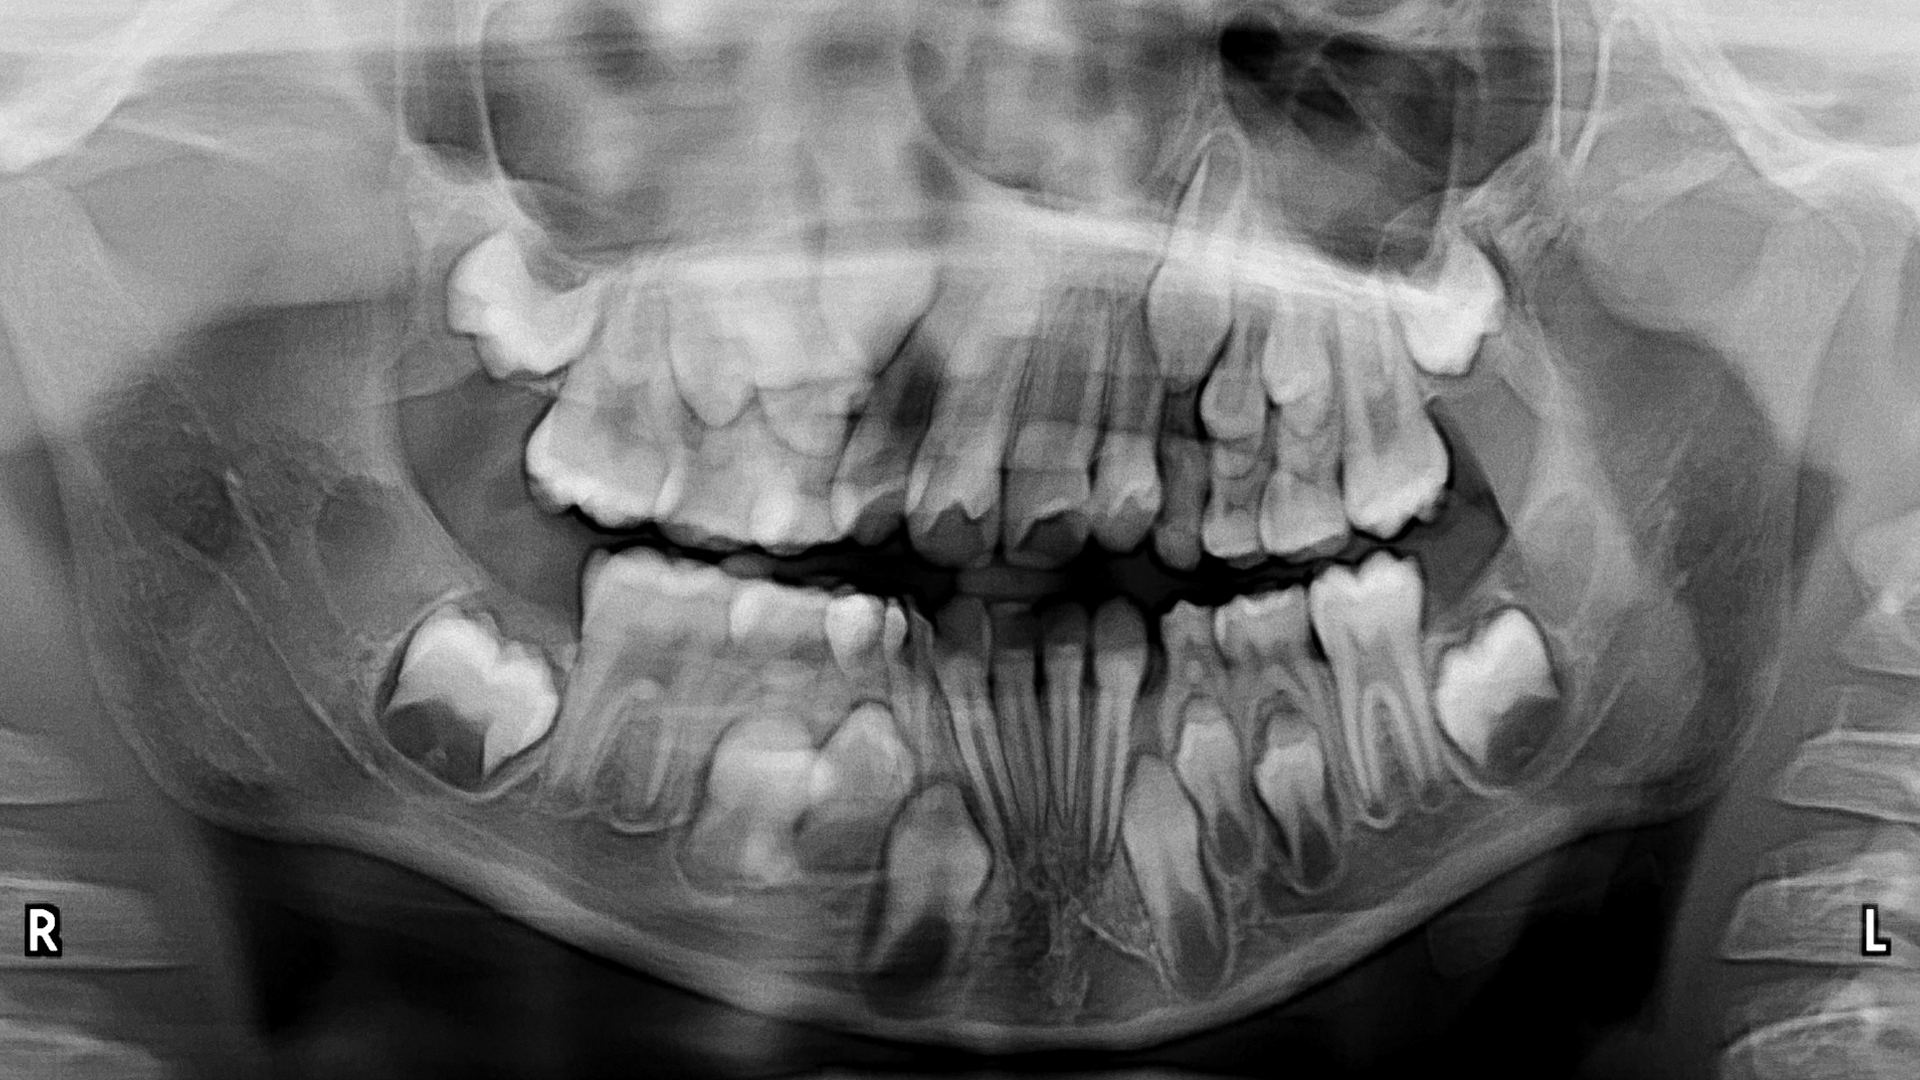

Recognizing the range of normal anatomical appearances on a well-made image is the most elementary step in image interpretation. At times, however, normal appearances can be altered as a result of patient anatomy, imaging system-related idiosyncrasies, or errors in patient positioning or image acquisition. Part 2 lecture will focus on the presentation of a systematic method of investigating panoramic images and variations in the presentation of normal anatomy.

- the range of appearances of normal anatomy on panoramic images.

- to identify key areas on the panoramic image where normal anatomy can be misdiagnosed as disease.